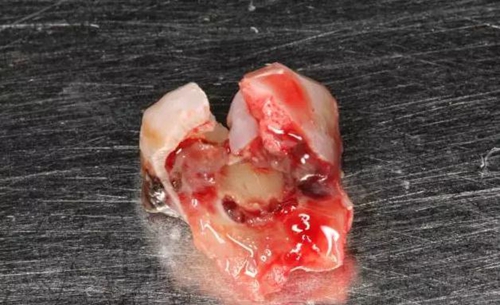

圖4.術后拔除的牙根:

13.jpg